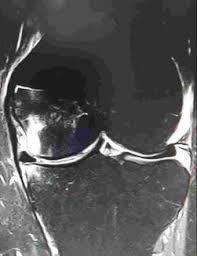

Alivio del dolor en artroplastia de rodilla

Trock D. et al Departamento de Medicina, Hospital de Danbury, CT. J. de Reumatología

De baja amplitud, de frecuencia extremadamente baja los campos magnéticos para el tratamiento de la artrosis de rodillas: un estudio clínico doble ciego.

Jacobson J. et.al. Inst. para la Investigación de Biofísica, en Jupiter, FL, EE.UU.

El tratamiento de impulsos magnéticos para la osteoartritis de rodilla: un estudio aleatorizado, doble ciego, controlado con placebo.